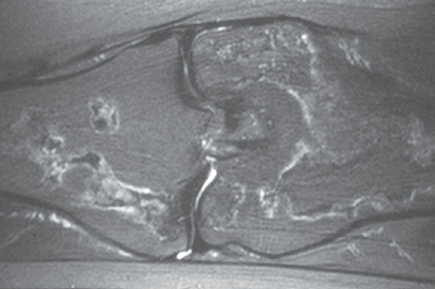

Due to the long-standing nature of the pain MRI of the knee was ordered. T1 and T2 (Figures 3-6) weighted images demonstrate serpiginous areas of increased and decreased signal paralleling each other consistent with the double line sign, which is classic for medullary infarcts of bone.

Figure 3. T2 weighted image in the coronal plane.

Figure 4. T2 weighted image in the sagittal plane.